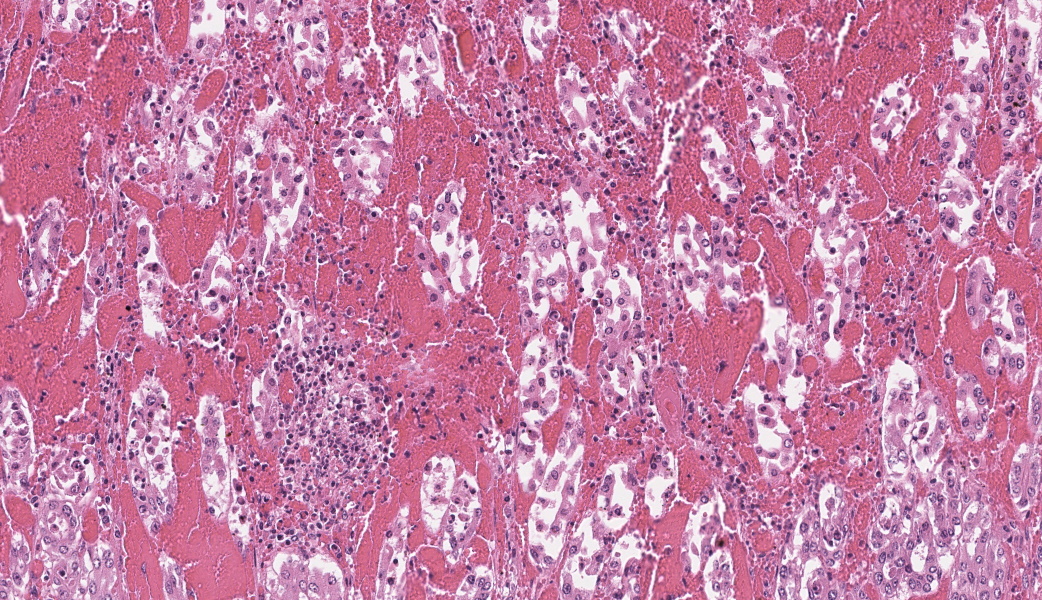

In the abomasum, focally extensive hemorrhage and edematous swelling were present in the lamina propria mucosa and in the submucosa, respectively. In the lamina propria mucosa, the capillary blood vessels and small veins showed severe congestion and hemorrhage. The endothelial cells of these vessels and arterioles had basophilic to amphophilic intranuclear inclusion bodies, of either full type or Cowdry type A. Occasionally, focal areas of necrotic mucosal epithelium were accompanied by neutrophil infiltration. In the submucosa, the endothelial cells of blood vessels had the same intranuclear inclusion bodies. Fibrinous and proteinous or serous materials were accumulated in some parts of the submucosal tissue. Neither bacteria nor fungi were detected by Gram and Giemsa stain, and by periodic acid-Schiff and Grocott methods, respectively.Contributor's Morphologic Diagnoses:

The present case was characterized pathologically by adenoviral hemorrhagic gastroenteritis and mycoplasmal caseonecrotic bronchopneumonia. The endothelial intranuclear inclusion bodies were detected histologically in the gastrointestinal tract (abomasum, duodenum, jejunum, ileum, cecum, colon, and rectum), liver, gallbladder, spleen, kidney and lung. The forestomach and brain contained no endothelial intranuclear inclusion bodies. In the abomasum, focal ulceration was associated with hemorrhagic abomasitis (No ulceration in the submitted sections). In the ileal Peyer's patch, lymphocytes were severely depleted. Epitheliotropic BAV inclusion bodies were not observed in any organs. By immunohistochemistry, the endothelial intranuclear inclusion bodies showed positive cross-reaction to anti-BAV type 7, weak cross-reaction to anti-BAV type 1, but negative for anti-BAV type 3 antisera. By transmission electron microscopy, the endothelial cells of hepatic sinusoids had paracrystalline arrays of adenovirus-like particles, 60-80 nm in diameter, in their nuclei.BAV belong to the family Adenoviridae, genera Mastadenovirus, and Atadenovirus.8 The serotypes of BAV-1, -2, -3, -9 and -10 belong to the genus Mastadenovirus, and the serotypes of BAV-4, -5, -6, -7, and -8 belong to the genus Atadenovirus.1,2,3,4,5,6,7,10 Serotypes 3, 4, 7, 10 have been associated with enteric disease.4,7,8 BAV, including serotypes 3, 7 and 10 has also been associated with respiratory disease.2,4,5,6 BAV-5 was isolated from a calf with weak calf syndrome, but not have been fully associated with severe gastroenteric disease.1

Abomasum: Abomasitis, necrohemorrhagic, acute, focally extensive, severe, with submucosal edema and endothelial intranuclear viral inclusions.JPC Comment:

The contributor’s write-up of bovine adenoviruses covered much of what was discussed in conference about this ubiquitous and relevant viral family. While the pathogenesis is not well-understood, the abomasum in this case had a significant, wedge-shaped hemorrhagic infarct on the H&E slide that tied in well to the current hypothesis on the pathogenesis of this virus. It is thought that viral targeting of endothelial cells and subsequent endothelial viral inclusions may disrupt blood flow to some degree, leading to turbulence and increased incidence of thrombosis of smaller vessels that can lead to ischemic infarcts.9 There was conversation on whether this should be morphed as an abomasitis or a vasculitis due to the endothelial targeting. It was ultimately the opinion of participants that this would not classify as true vasculitis due to the lack of inflammation in vessel walls.